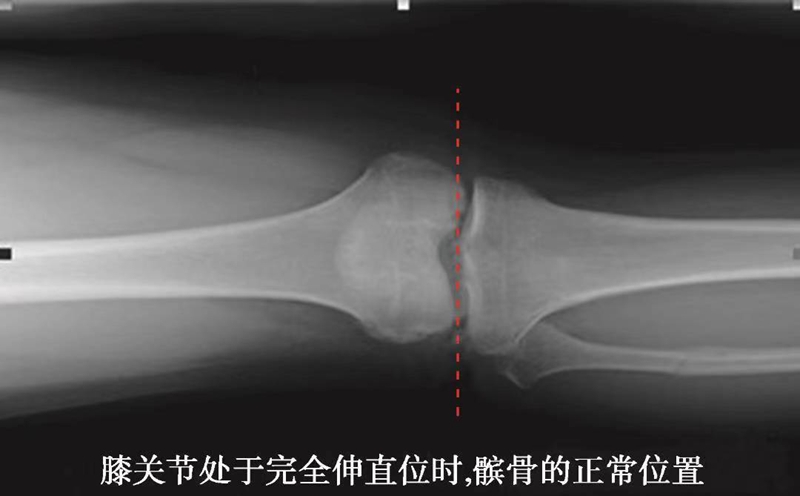

正常髌骨中心点应位于下肢轴线上或稍内侧(图1)。对于髌骨不稳定,膝关节正位像可见髌骨偏离正常的位置,向外侧移位(图2、图3)。

图1 正常膝关节正位X线平片显示了髌骨的正常位置